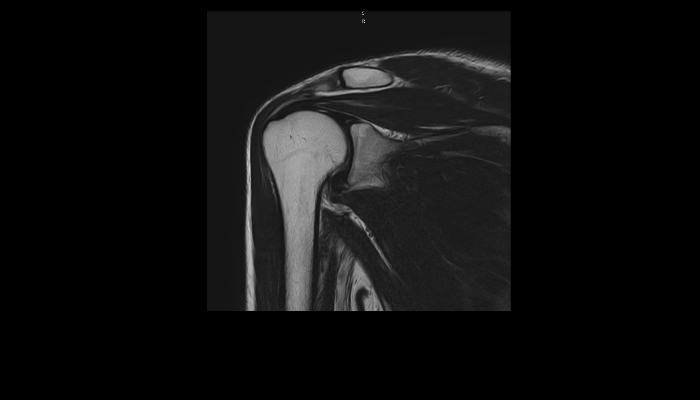

頭部MRI画像 頭部MRI脳腫瘍や脳梗塞、認知症など脳の病気を詳細に評価します。 MRA画像 頭部MRA造影剤を使わずに脳の動脈を描出します。動脈瘤や狭窄を検索します。 脊椎MRI画像 脊椎MRI椎間板ヘルニアや脊柱管狭窄症など脊椎や脊髄の疾患を評価します。 腹部MRI画像 上腹部MRI・MRCP肝臓・胆のう・膵臓・腎臓などの上腹部の重要臓器を詳細に評価します。 乳房MRI画像 乳腺MRIマンモグラフィや超音波と併せて、乳がんを検索や病変の範囲を評価します。 前立腺MRI画像 前立腺MRI前立腺がんを検索します。PSA高値の方はまず前立腺MRIをお勧めします。 子宮・卵巣MRI画像 子宮・卵巣子宮筋腫や子宮体癌、卵巣腫瘍など女性特有の病気を評価します。 膝関節MRI画像 膝関節膝関節の骨や靭帯、半月板を評価します。靭帯断裂や半月板損傷などレントゲンでは評価できない構造も診断できます。 肩関節MRI画像 肩関節肩関節の骨や腱、靭帯を評価します。腱板断裂や腱の断裂などレントゲンでは評価できない構造も診断できます。 心臓MRA 心臓MRA狭心症、心筋梗塞の原因となる冠動脈の狭窄を評価します。造影剤を使用せず、撮影可能です。 DWIBS画像 DWIBS全身のがんを広く検索します。リンパ節や転移の評価にも優れます。